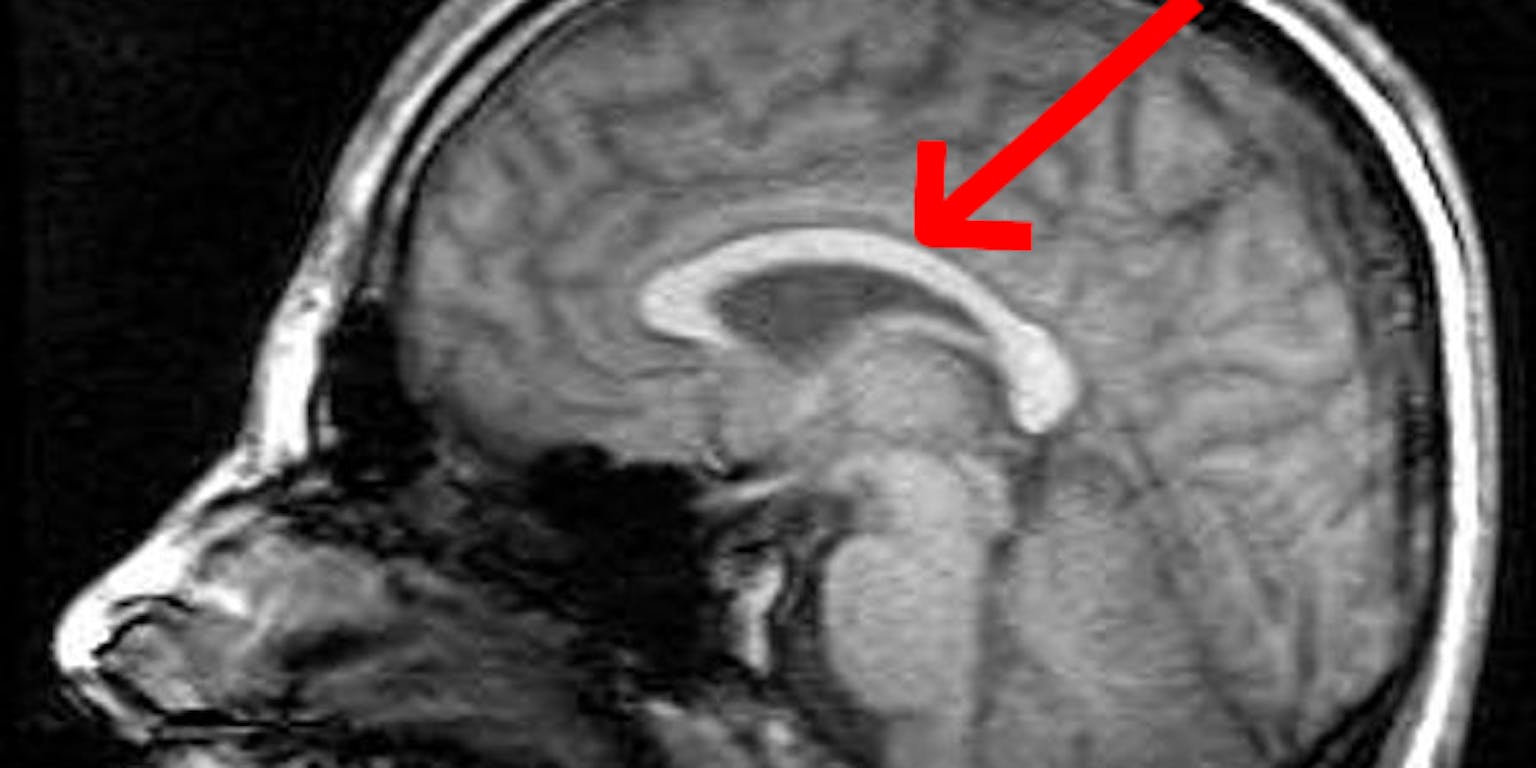

Daarnaast zijn er verschillen in het magnetische veld en dat moet gelijk worden gemaakt om goede scans te kunnen krijgen. Tussen de verschillende scans door kunnen wij praten met de proefpersoon. Dan vragen wij even hoe het gaat en vertellen wij dat wij nog iets moeten instellen voordat de taak begint. Elk brein is echt heel anders en dat is wel heel bijzonder om te zien. Je kan bijvoorbeeld verschillen zien in de grootte en dikte van de hersenbalk, of het corpus callosum (de verbinding tussen de linker en rechter hersenhelft) (zie MRI-scans).